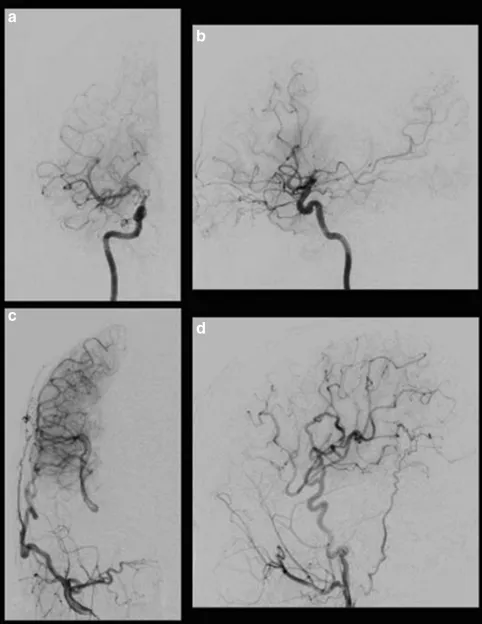

术后即刻在镇静状态下进行Xe-CT检查,以评估高灌注状态。局部高灌注区在搭桥术中被观察到,术后过程顺利。病人没有出现谵妄、癫痫、头痛和新的神经功能缺损等并发症,术后5天和7个月MRI未见缺血性病变。MRA显示STA在7个月内有发展和扩张,选择性右颈外动脉造影显示右侧大脑中动脉区域有大量的血供(图3)。

图3:术后右颈动脉造影显示经右侧大脑外动脉的旁路血流通过MCA和ACA供应到灌注较少的区域。右侧颈内动脉正位(a)、侧位(b);右颈外动脉正位(c)、侧位(d)。